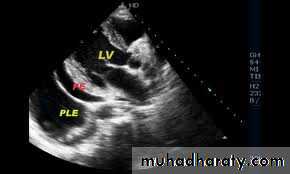

What are useful investigation?Pericardial effusion

Echo :50 ml detected

Ecg + CXR + ECHO

-Echo free zone surround the heart

-Fluid aspiration-Pericardial protein /serum protein > o.5 exudateAdenosine deaminases –sensitive and spesefic in TB

ECHO-

Free zone surround heartRT atrial and ventricular collapse

Dilated inferior vena cava